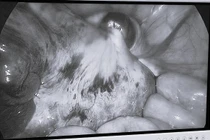

Đau bụng vùng hố chậu phải, kèm theo nôn ói, bệnh nhi được gia đình cho uống thuốc nhưng không cải thiện, đi khám phát hiện khối u buồng trứng trái bị xoắn hiếm gặp.

Gia đình bé Đào Minh Anh (12 tuổi, Hải Phòng) phát hiện ra con mình có biểu hiện bụng to hơn bình thường nhưng thấy con không có biểu hiện nào khác nên cha mẹ chủ quan không đưa con đi khám. Đến khi thấy bụng con quá to, sờ thấy u gia đình mới đưa đi khám thì u buồng trứng đã quá lớn, nặng tới 3 kg nên các bác sĩ đã phải cắt bỏ hoàn toàn một bên buồng trứng của bệnh nhi.